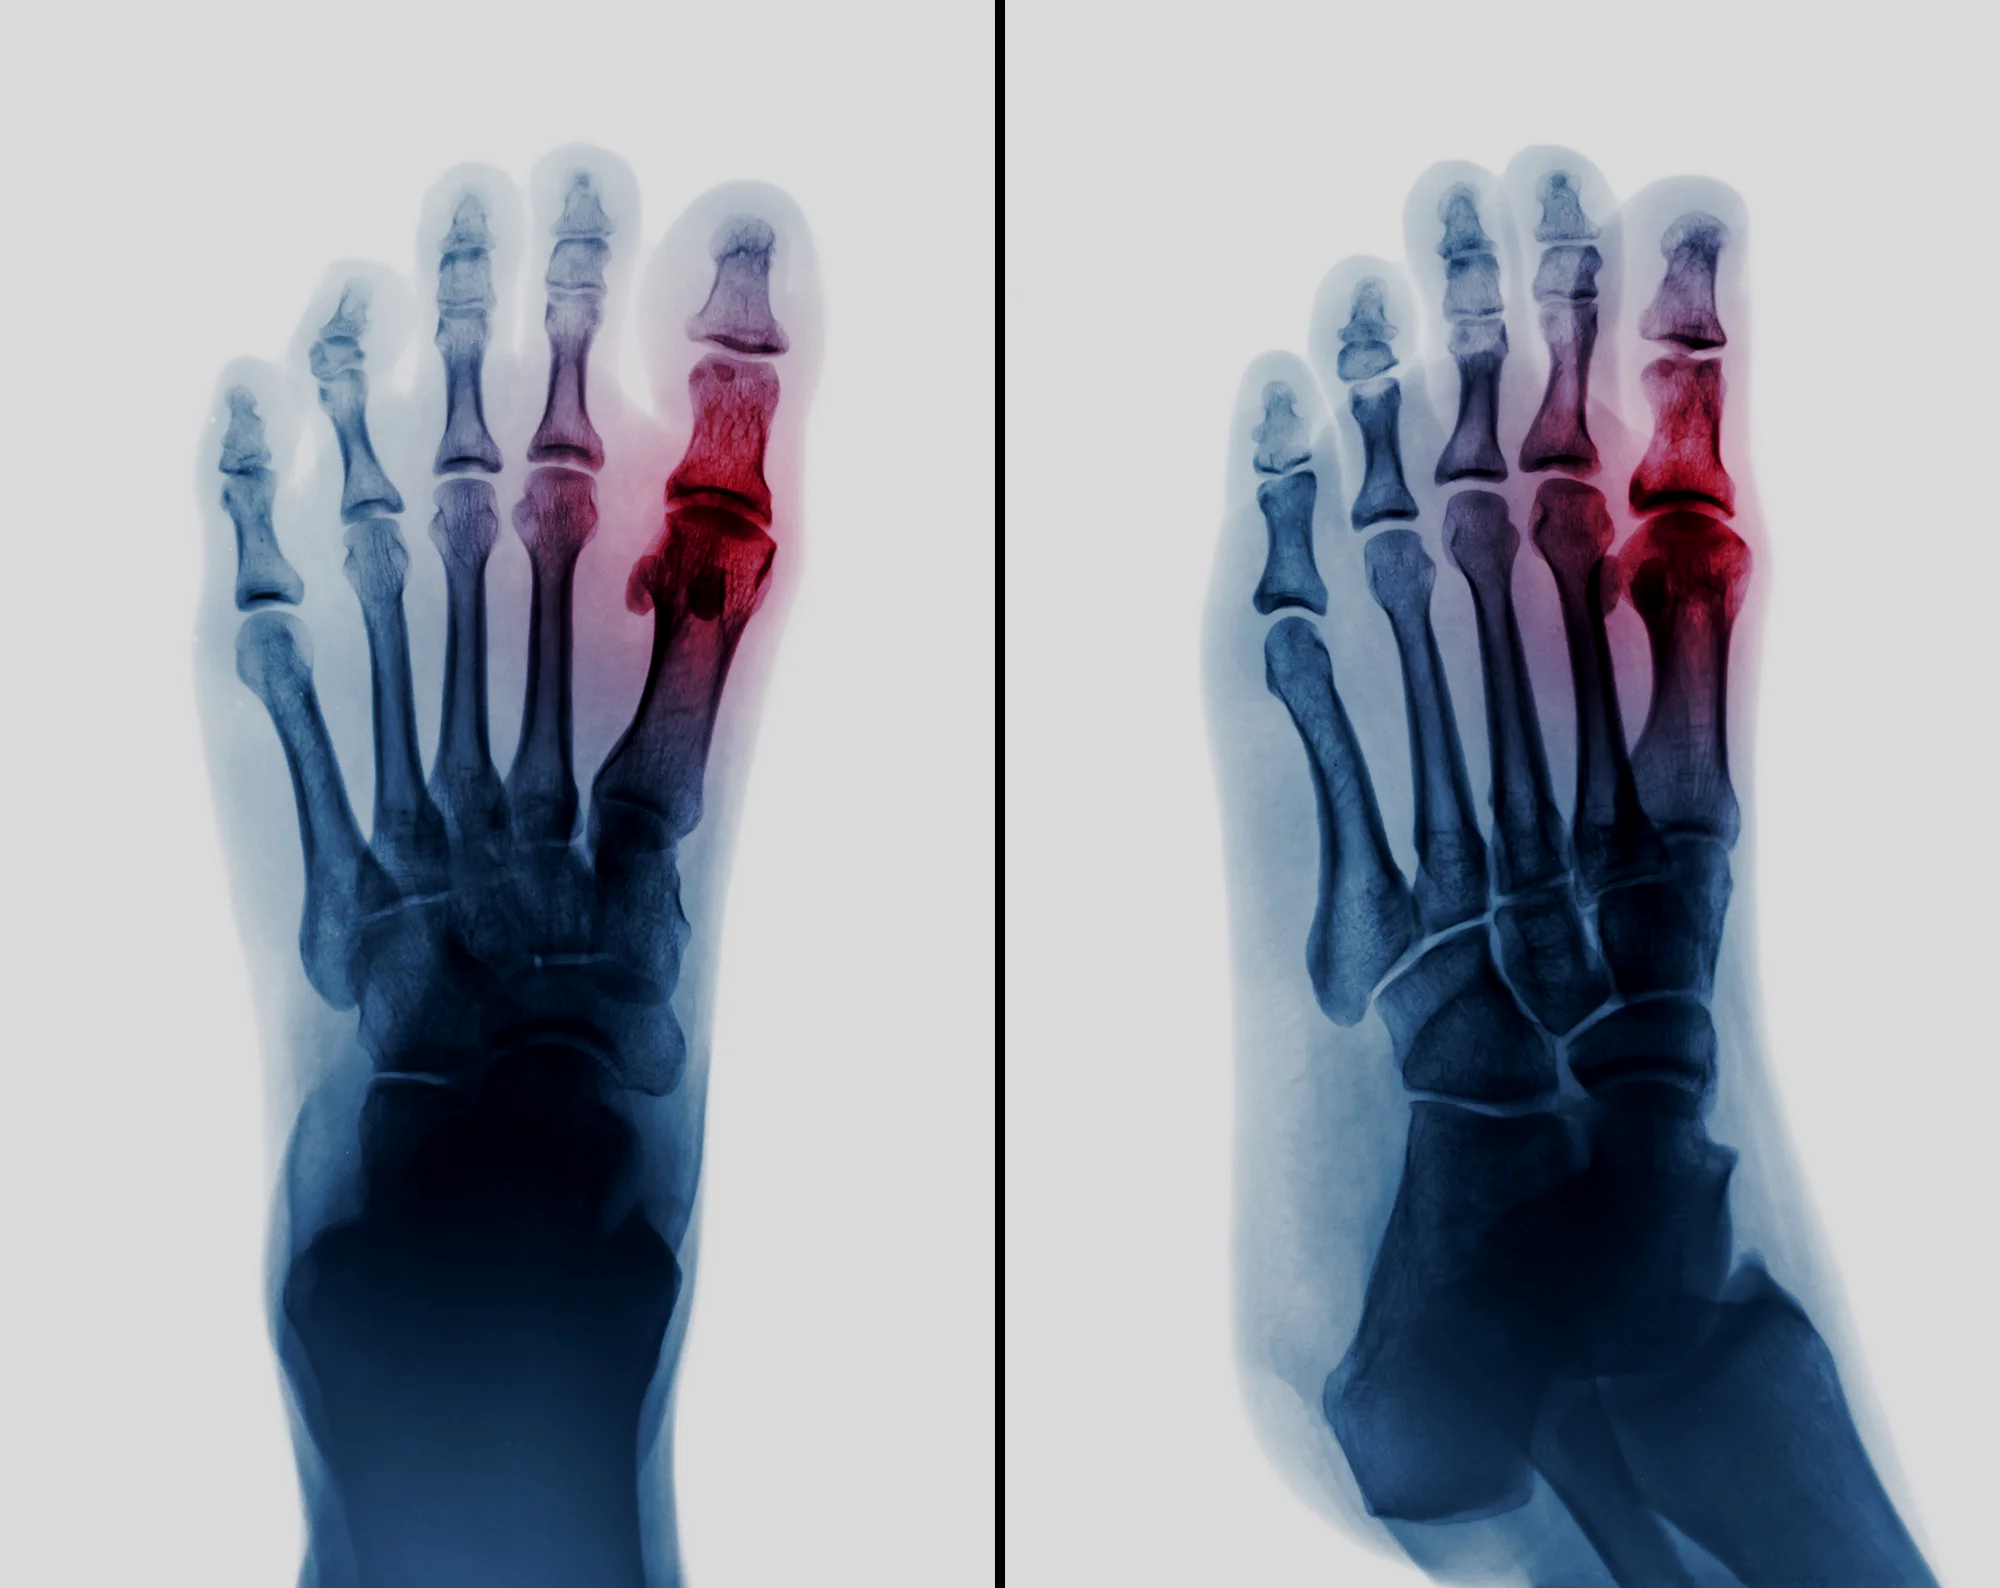

Foot Arthritis

Osteoarthritis

This is a condition where the cartilage wears out due to abnormal wear and tear. Read more >>

Metatarsalgia

You have got metatarsalgia which means pain in the ball of the foot. This may affect just one joint or several joints.  Read more >>

Forefoot Reconstruction

Rheumatoid arthritis causes many or all of the toes to buckle and deform, making the joints in the forefoot prominent.  Rubbing on the joints makes them red and painful. Read more >>